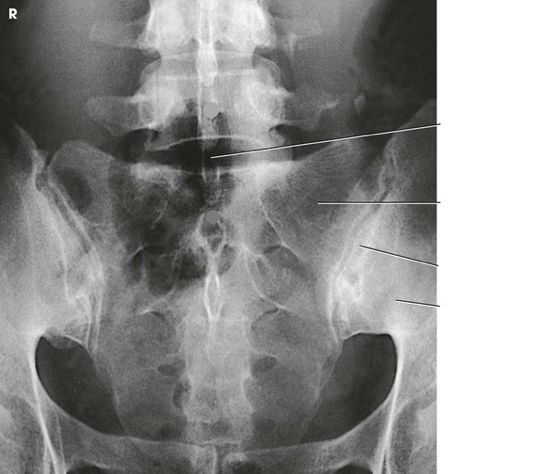

Question

Label the image

9431e827-b310-4f35-8608-b13fac341ce0 (image/png)

Answer

L5

pars interarticularis

transverse process

zygapophyseal joint

inferior articular process

pedicle

superior articular process